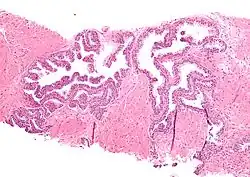

Micrograph showing high-grade prostatic intraepithelial neoplasia. H&E stain.

Histopathology of high-grade prostatic intraepithelial neoplasia (HGPIN) with typical features, H&E stain.[6]

Microscopically, PIN is a collection of irregular, atypical epithelial cells. The architecture of the glands and ducts remains normal. The epithelial cells proliferate and crowding results in a pseudo-multilayer appearance. They remain fully contained within a prostate acinus (the berry-shaped termination of a gland, where the secretion is produced) or duct. The latter can be demonstrated with special staining techniques (immunohistochemistry for cytokeratins) to identify the basal cells forming the supporting layer of the acinus. In prostate cancer, the abnormal cells spread beyond the boundaries of the acinus and form clusters without basal cells. In HGPIN, the basal cell layer is disrupted but present. PIN is primarily found in the peripheral zone of the prostate (75-80%), rarely in the transition zone (10-15%) and very rarely in the central zone (5%), a distribution that parallels the zonal distribution for prostate carcinoma.[7]

Several architectural variants of PIN have been described, and many cases have multiple patterns. The main ones are tufting, micropapillary, cribriform, and flat. Although these different appearances may cause confusion with other conditions, they have not been found to be of clinical importance. Rarer types are signet-ring-cell, small-cell-neuroendocrine, mucinous, foamy, inverted, and with squamous differentiation.[3]